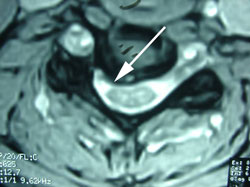

Figure 5 is a lateral MRI view of the spine shown on x-ray in Figures 1-4. At the arrow is the disc herniation, in this case at the C5-C6 level, where we see the instability and backward movement of the C5 vertebra on C6 below it. This disc herniation is also shown in Figure 6 below in an axial or cross cut view through the disc space at C5-C6 showing the disc herniation compressing the nerve to cause the arm pain that this patient complains of.  (See the large arrow.)

active inflammation in the cervical spine disc

Note in Figure 6, at the small arrow, the white dense material within the disc herniation; this signifies active inflammation within the disc and such inflammation is considered a source of pain. Also note that this disc herniation also contacts the spinal cord as shown at the yellow arrow.